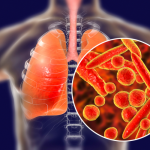

HƯỞNG ỨNG NGÀY THẾ GIỚI PHÒNG CHỐNG LAO 24/3

Chúng ta có thể chấm dứt bệnh lao.

Bệnh lao có thể chữa khỏi hoàn toàn nếu phát hiện sớm và điều trị kịp thời,...